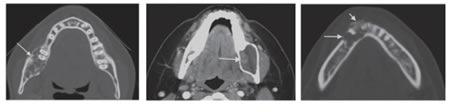

Figure10: Ameloblastoma. (A) Axial bone CT shows the multi-septated or loculated appearance of the multicystic ameloblastoma. Also, it shows course septations and the eccentric expansion (arrow). (B)Axial contrast-enhanced CT of a unicystic ameloblatoma demonestrates a cystic lesion eccentrically expanding the buccal and lingual cortices. The enhancing mural nodule (arrow) is a characteristic feature for ameloblastoma. (C) Axial bone CT of a desmoplastic type of ameloblastoma. The expansile lobulated and loculated mass (long arrow) is

characteristic for ameloblastoma; the more anterior location is less common. However, the location, aggressive sclerotic changes and periosteal reaction (short arrow) are seen more often in this type.

10